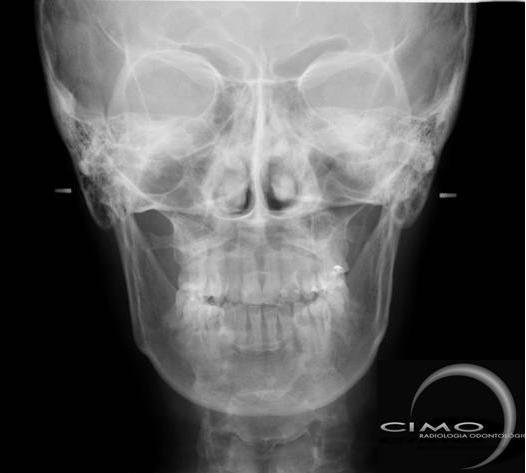

TELERRADIOGRAFIAS

Lateral e Frontal

Radiografias do crânio, realizadas a uma distância pré-estabelecida, com o objetivo de diminuir distorções, com o auxílio de um artefato posicionador – cefalostato. Permite mostrar os ossos da face e crânio para avaliação do crescimento, desenvolvimento, relação esqueletal, simetria, estudo de adenóides, processos patológicos e traumáticos. São exames utilizados na prática cirúrgica e ortodôntica, como base para análises cefalométricas, tanto manual como computadorizada.

* Telerradiografia Frontal